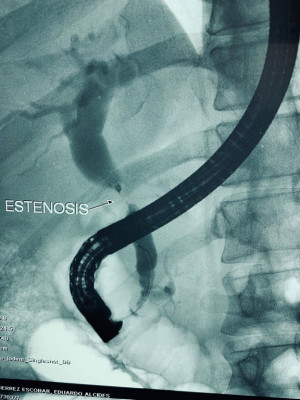

Cálculo gigante por coledocoliatisis